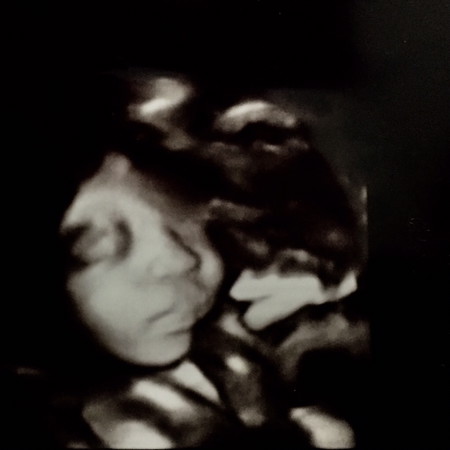

แม่ๆบ้านไหนซาวด์4มิติมาแล้วลูกตรงปกบ้างคะ อวดรูปกันหน่อยคะ

ซาวด์ตอน 32 week ตอนนี้ 36+2 ค่ะ หมอนัดผ่าคลอด 15มิย.นี้ น้องไม่ยอมกลับหัว

ตรงปกไหม คลอดออกมา นน. 3,753 ค่ะ ตอนนี้ 1 เดือน 29 วัน

แบบนี้ตรงปกไหมคะ ตอนนี้ 2เดือน 7วันค่ะ

30สัปดาห์กับแรกเกิดค่ะ

ซาวตอน 22+1 รอลุ้นเหมือนกันค่ะ